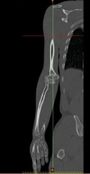

Mimics software (Ver.10, Materialise NV., Belgium), through computed tomography (CT), was used to construct elbow bones. CT data set involved the slice thickness of 0.7mm and the resolution of 0.477mm (Figure 1). Then, the constructed elbow bones were imported into SolidWorks. In this study, SolidWorks software was used for simulated surgery and modeling all components of linked elbow implant. Simulated surgery of humerus and ulna bones was carried out to insert modeled implant into constructed bone. Therefore, a hole was made in humerus/ulna bones and the implant left these bones with a hole. The initial step to prepare of the humerus was bone resection from the midportion of the capitellum and trochlea (Figure 2). As a result, the center axis of flexion-extension was identified. If the capitellum is assumed a circle and sighted from the lateral position of the elbow, the center axis of rotation is placed in the center of the circle. The similar procedure was carried out to prepare ulna (Figure 3). The ulnar component was inserted into the ulna to ensure a good fit before cementing. Conventional cemented fixation was the basis of modeling of all stems therefore, they had smooth surfaces. The optimum thickness of cement (between 1.0 and 1.5 mm) was considered to avoid high failure in cement-bone [26].

Draft Heidari 601543490-image1.jpeg

Draft Heidari 601543490-image2.jpeg

(a) (b)

Figure 1. (a) CT data (b) Constructed bone from CT scan data